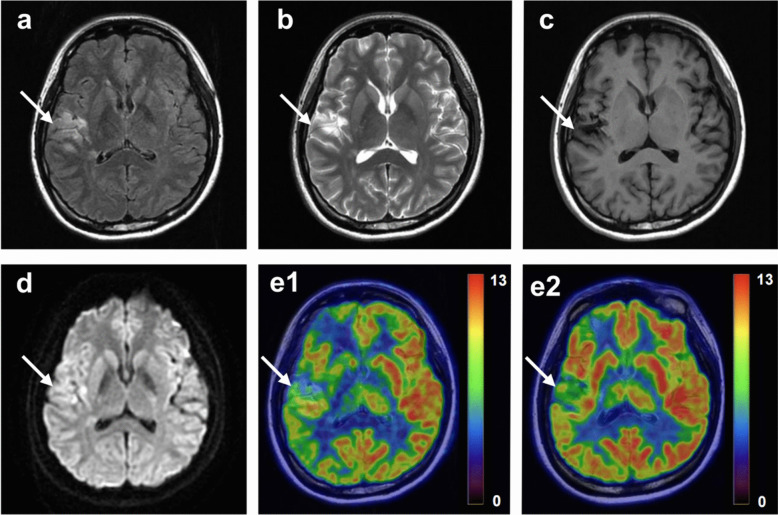

Procedures: Seventy patients diagnosed with subacute and chronic ischemic stroke were retrospectively analyzed. All patients underwent 2-deoxy- 2-[18F]fluoro-D-glucose ([18F]FDG) PET/MR scans and were assessed using the National Institutes of Health Stroke Scale (NIHSS) and the Modified Rankin Scale (mRS). Nineteen patients underwent a repeat [18F]FDG PET/MR scan one year later. Two voxel-wise AI methods, designated as AI1 and AI2, were calculated based on standardized uptake value ratio (SUVR). The hypometabolism on affected side assessed by different AI methods were compared. The correlations between the hypometabolism and the clinical scores were analyzed.

Results: The volume and percentage of decreased [18F]FDG metabolism assessed by AI2 was larger than that obtained from AI1 (all p < 0.0001). The correlation coefficients between the clinical scores and the decreased metabolism in temporal and parietal lobes assessed by AI1 method were all higher than those from AI2. In addition, the improved follow-up patients showed more pronounced metabolic improvement as assessed by AI1.

Conclusions: The assessment of cerebral [18F]FDG metabolism in patients with unilateral internal carotid/middle cerebral artery steno-occlusion to reflect clinical neurological function using the AI1 method demonstrated superior performance in comparison to the AI2 method.